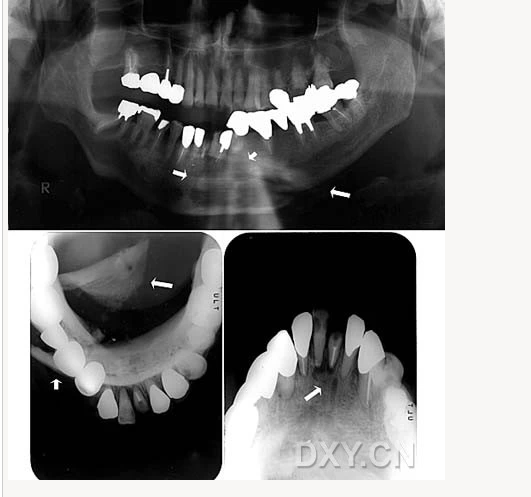

成釉細胞瘤

涎石病

骨髓炎

頜骨骨折